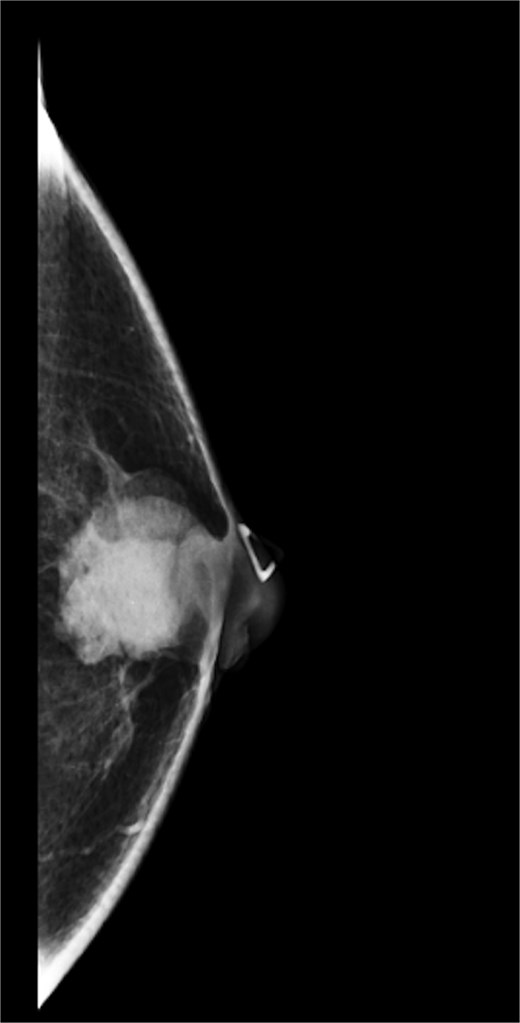

A 63-year-old male with a past medical history of heavy daily tobacco use, COPD, and a left breast leiomyoma diagnosed in 2018 presented to a general surgeon with a nonhealing left breast abscess. The patient had a persistent 3 cm retroareolar mass despite multiple incision and drainage procedures. On exam, the left axillary lymph nodes were unremarkable and the nipple, while not inverted, was chronically distorted, indurated, and inflamed. The persisting mass and inflammation were initially concerning for inflammatory breast cancer. Superficial biopsy by both a dermatologist and general surgeon were equivocal. Diagnostic mammogram and targeted left breast ultrasound revealed a retroareolar 3.3 × 3.6 × 2.7 cm heterogenous mass, corresponding to the area of palpable concern (Figs 1 and 2).

Diagnostic mammogram of left breast showing heterogenous retroareolar mass – second view.